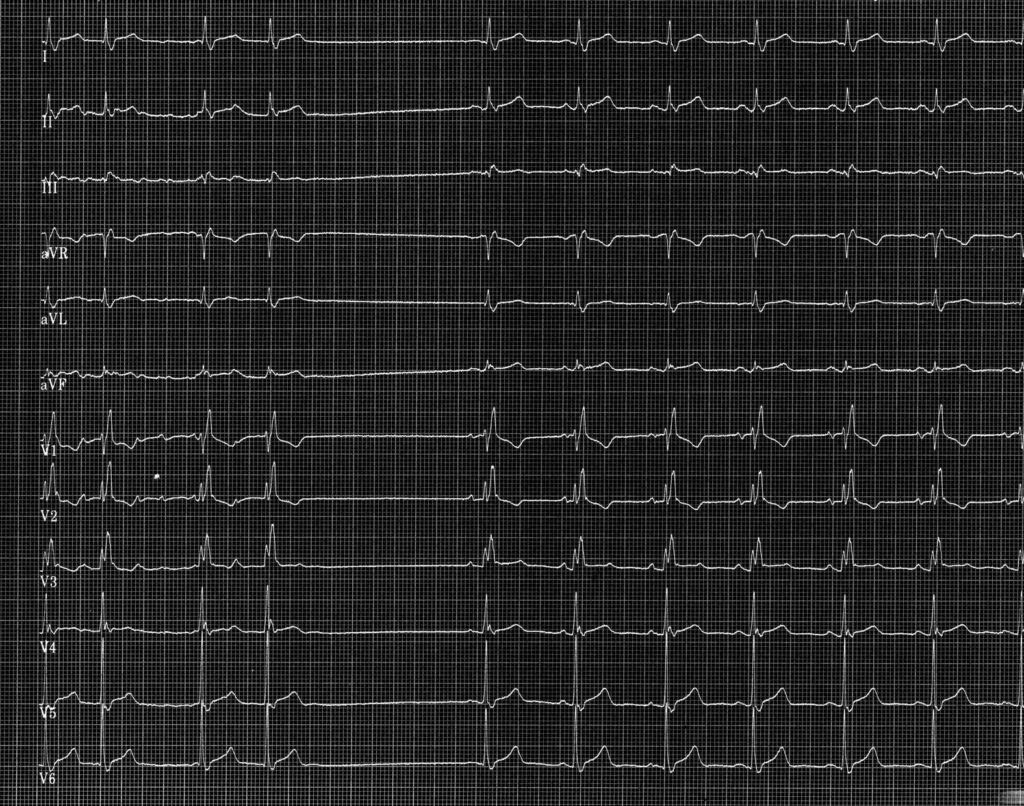

Tracé 2.8: Pause sinusale post-réduction de fibrillation auriculaire

Homme de 74 ans présentant des syncopes répétées avec sensation de palpitations précé­ dant la perte de connaissance. Enregistrement d’un tracé lors de la survenue de palpita­tions.

Au début du tracé, l’activité atriale est irrégulière, très rapide, anarchique et correspond à une FA conduite avec bloc de branche droit complet (QRS > 120 ms, aspect rsR’ en V1, onde S large et trainante en V6); l’arythmie atriale se réduit avec mise en évidence d’une pause sinusale post- réductionnelle de plus de 2 secondes; reprise d’une activité sinusale normale avec le même aspect de bloc de branche droit.

Ce type de tracé correspond à une variante de la maladie de l’oreillette, associant épisodes de fibrillation auriculaire et pause survenant uniquement au moment de la réduction de l’arythmie. Les palpitations étaient en rapport avec les épisodes de fibrillation auriculaire paroxystique, les syncopes avec la survenue de pauses post- réductionnelles. Pour prévenir la survenue de syncope dans ce cadre, 2 stratégies sont envisageables. La première est de considérer que la pause post-réductionnelle n’est que la conséquence de l’arythmie et que le traitement doit cibler la fibrillation atriale. Une étude avait montré que chez ce type de patients, l’ablation des veines pulmonaires permettait d’éviter les récidives d’arythmie mais également permettait de supprimer les syncopes. La seconde stratégie est de considérer que la pause post-réduction traduit l’existence d’une dysfonction sinusale révélée à la réduction justifiant la pose d’un stimulateur cardiaque.

La survenue d’une pause sinusale post-réductionnelle sur un épisode d’arythmie atriale doit être évoquée chez un patient présentant une fibrillation auriculaire ou un flutter et une syncope.